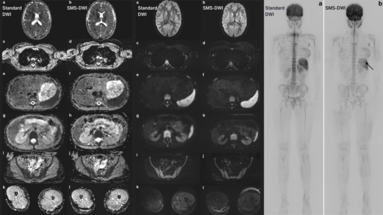

Advancing Neuro-Oncology Assessments: Mint Medical to Integrate Newly Published RANO 2.0 Criteria into mint Lesion™

Glioblastomas and other gliomas are the most common malignant primary brain tumor types, yet few effective therapies are available. Clinical research and clinical trials are essential in supporting…